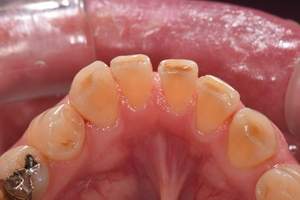

歯石除去

治療前

治療後

| 年齢 | 36歳・男性 |

| 主訴 | 歯石をとりたい |

| 治療内容 | 歯石除去 |

| 治療期間 | 30分 |

| 費用 | 約2,000円 |

| リスク・副作用 | ・歯ぐきの炎症が強いと歯石を取る際に出血することがあります。 ・処置後に歯がしみることがあります。 ・歯と歯の間に隙間ができるので、息が漏れ発音しにくいと感じることがあります。 ・歯ぐきの炎症が軽減すると歯ぐきが引き締まり、歯が長く見えることがあります。 |